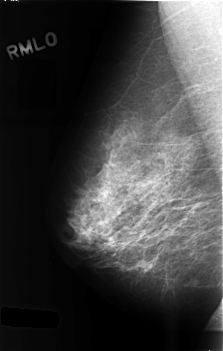

C_0487_1.RIGHT_MLO

RIGHT_MLO LINES 4552 PIXELS_PER_LINE 2896 BITS_PER_PIXEL 12 RESOLUTION 50 NON_OVERLAY